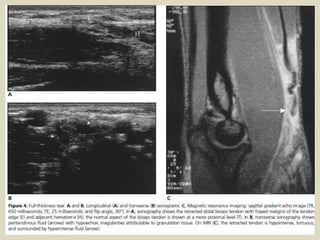

Rupture of the distal biceps tendon

is uncommon and it is usually due to attempting to lift

a heavy weight. Complete ruptures usually cause pain

and a clinically palpable defect so it is not difficult to

diagnose. In complete tears without muscle retraction,

when there is an important soft-tissue swelling with

difficult clinical examination or in partial ruptures,

imaging may be required. The complete rupture of the

tendon produces a defect at the expected location of

the tendon. The gap is filled with hematoma, and the

retracted tendon edge may be visible. Anomalies of

the median nerve can also be demonstrated. We show

a case of iatrogenic neuropathy after venopuncture.

(a, b) Longitudinal (a) and transverse (b) US images show a moderate

partial tear of the distal biceps tendon (arrows in a, arrowheads in b).